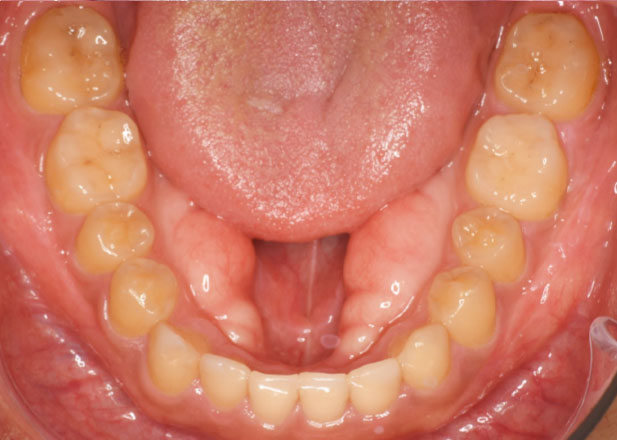

口腔内写真

治療前

治療後

主訴 正中離開(すきっ歯)を治したい。